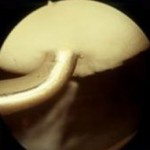

Desde hace muchos años, venimos desarrollando esta técnica para defectos focales del cartílago. Con ella logramos restituir no sólo el cartílago sino también el hueso subcentral, es decir, lo que a nosotros nos gusta denominar «unidad osteocondral». Utilizamos injertos tomados de la propia rodilla del paciente (zona donante) que se insertan en el área dañada. Es la técnica de elección en deportistas de alta demanda (fútbol, baloncesto, pádel, etc) con unos resultados de vuelta al deporte por encima de otras técnicas como el cultivo de condrocitos o las microfracturas. Se utiliza sobre todo en rodilla pero también la hemos empleado para lesiones de tobillo (astrágalo) y hombro. A continuación, mostramos varios casos de mosaicoplastia

- mosaicoplastia abierta

- Mosaicoplastia + sutura de menisco

- Mosaicoplastia con 3 cilindros osteocondrales en cóndilo femoral

- Mosaicoplastia artroscópica de rótula según técnica personal